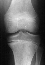

Radiographs: AP/Lateral of left knee from September of 1995 demonstrate

a mild varus deformity with an estimated metaphyseal/diaphyseal angle of

8o. There is also evidence of widening of the medial 1/3 of

the proximal tibial physis

The AP of the left knee in May of 1996 shows worsening of the varus deformity

with a metaphyseal/diaphyseal angle of 14o. There is increased

widening of the medial proximal tibial physis with evidence of sclerosis.